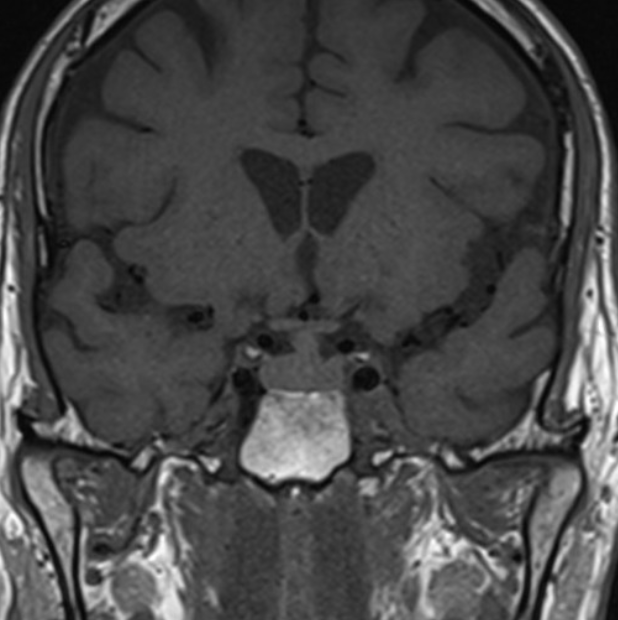

CT and MRI

Both CT and MRI can be used to delineate the malformation cross-sectionally.

MR angiography

The dilated feeding and draining vessels appear as flow-voids on T2. MRA may also be performed which would better delineate vascular anatomy.

Angiography

Angiography remains the gold standard in full characterisation of the lesion. It enables to individually catheterise feeding vessels. Morphologically a spherical or ellipsoid varix may be visualised. Venous drainage is via the median prosencephalic vein (MPV), the straight sinus (if present) and then out via the transverse/sigmoid sinuses. By definition, there should be no drainage to other components of the deep venous system 6.